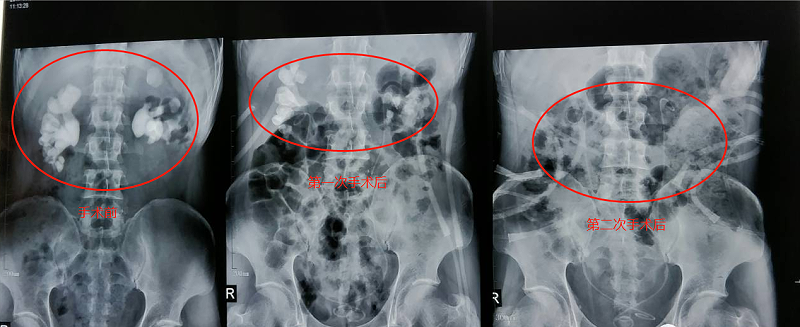

11月8日,雅安仁康醫(yī)院采用上述方案為患者進(jìn)行了雙側(cè)經(jīng)皮腎鏡碎石取石術(shù)。手術(shù)進(jìn)行了兩小時,幾乎沒有出血,術(shù)后也沒有出現(xiàn)其他并發(fā)癥。手術(shù)后復(fù)查X線照片顯示,右腎結(jié)石已清除一半,左腎結(jié)石清除70%。在病人身體恢復(fù)后,11月14日病人又進(jìn)行了二次手術(shù),依然采用第一次方案,采用雙側(cè)同時經(jīng)皮腎鏡碎石取石。術(shù)后復(fù)查X線照片顯示雙腎“巨無霸”結(jié)石已消失。目前,洛大叔腎功能已恢復(fù)正常,身體情況也恢復(fù)良好,沒有出現(xiàn)術(shù)后并發(fā)癥,準(zhǔn)備近期出院。

腎結(jié)石對比

檢查照片對比圖